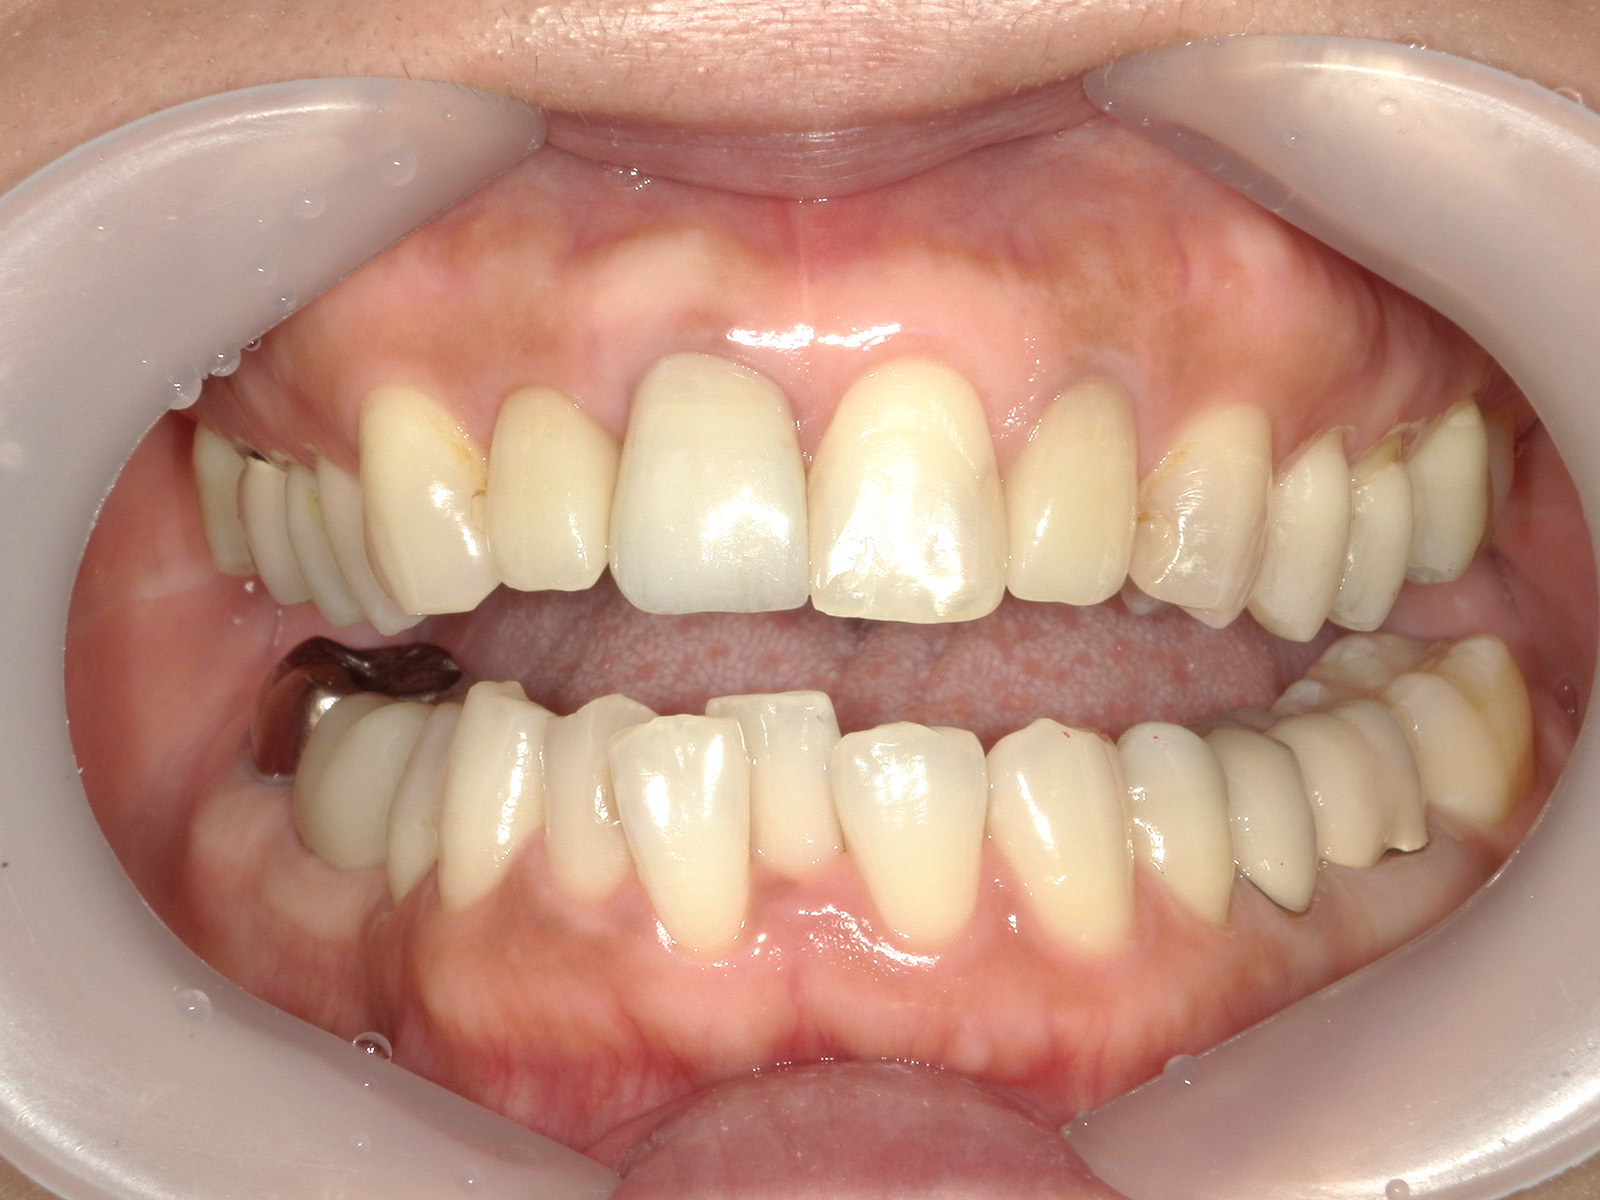

• 治療前

• 治療後

主訴左上の前歯がうずく感じがする 歯ぐきのラインがそろっていないのが気になる

どのように治療したのかの具体的な説明歯の軸のズレを直すために矯正治療行った後にそのままではかぶせ物がかぶせられないので、クラウンレングスニング(歯茎を切って開いて、歯を支えている骨を整える処置)したのちに上の4前歯ジルコニアクラウンにて修復

治療期間矯正期間含めて約2年

治療費206.8万

その治療をすることで起こり得るリスク歯根(歯の土台部分)が短くなることによる、動揺や破折のリスクがあがる